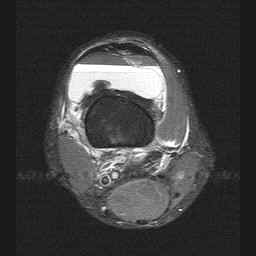

Image 3: Axial STIR image demonstrating the supression of fat (superior layer) on this sequence with bright serum layering on dependant cellular components of blood. CLICK TO ENLARGE.